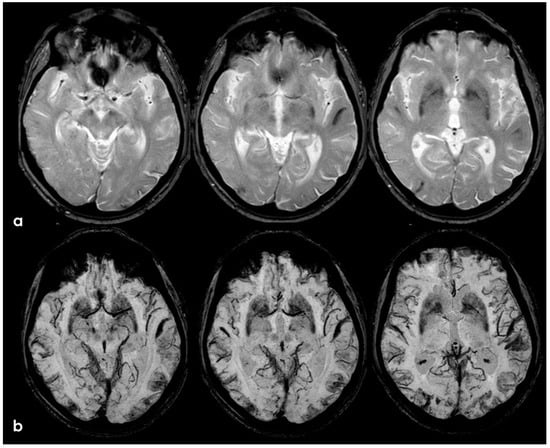

6. December 2017: Recurrent SAH